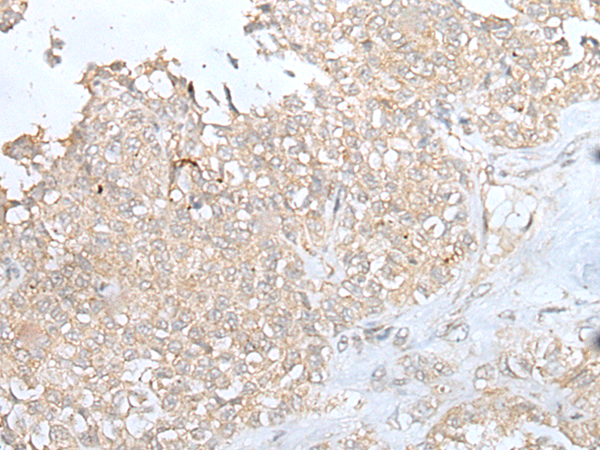

IHC positive control: |

Human ovarian cancer |